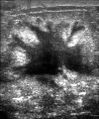

يتضمن الفحص السريري أو الذاتي للثدي تحسس الثدي للوقوف على وجود كتل أو أي تشوهات أخرى. يتم إجراء فحوصات الثدي السريرية من قبل مقدمي الرعاية الصحية، بينما تُجرى فحوصات الثدي الذاتية من قبل الشخص نفسه.[109] لا تدعم الأدلة فعالية أي من نوعي فحوصات الثدي، لأنه بحلول الوقت الذي يصبح فيه الورم كبيرًا بما يكفي ليتم اكتشافه، من المحتمل أن ينمو لعدة سنوات وبالتالي يصبح كبيرًا بما يكفي ليتم لاكتشافه بدون فحص.[110][111] يستخدم فحص التصوير الإشعاعي لسرطان الثدي بالأشعة السينية لفحص الثدي بحثًا عن أي كتل. أثناء الفحص، يتم ضغط الثدي ويلتقط الفني صورًا من زوايا متعددة. يلتقط التصوير الشعاعي للثدي العام صورًا للثدي بأكمله، بينما يركز تصوير الثدي الشعاعي التشخيصي على كتلة معينة أو منطقة معينة مثيرة للقلق.[112]

يمكن أن توفر طريقتا الفحص الأكثر شيوعًا، وهما الفحص البدني للثدي بواسطة مقدم الرعاية الصحية والتصوير الإشعاعي للثدي، احتمالًا تقريبيًا لوجود كتلة سرطانية، وقد تكتشف أيضًا بعض الآفات الأخرى، مثل الكيسات البسيطة.[122] عندما تكون هذه الفحوصات غير حاسمة، يمكن لمقدم الرعاية الصحية أخذ عينة من السائل الموجود في الكتلة لتحليلها مجهريًا (إجراء يُعرف باسم الخزعة بالإبرة) للمساعدة في تحديد التشخيص. يمكن إجراء الخزعة بالإبرة في عيادة أو مكتب مقدم الرعاية الصحية. يمكن استخدام مخدر موضعي لتخدير أنسجة الثدي لمنع الألم أثناء العملية، ولكن قد لا يكون ضروريًا إذا لم يكن الورم تحت الجلد. إن اكتشاف وجود سائل واضح يجعل الكتلة غير سرطانية إلى حد كبير، ولكن قد يتم إرسال السائل الدموي للفحص تحت المجهر بحثًا عن الخلايا السرطانية. يمكن استخدام الفحص البدني للثدي، والتصوير الشعاعي للثدي، والخزعة بالإبرة معاً لتشخيص سرطان الثدي بدرجة جيدة من الدقة.

تصوير الثدي يظهر ثدياً طبيعياً (اليسار) وثدياً مصاب بالسرطان (اليمين).